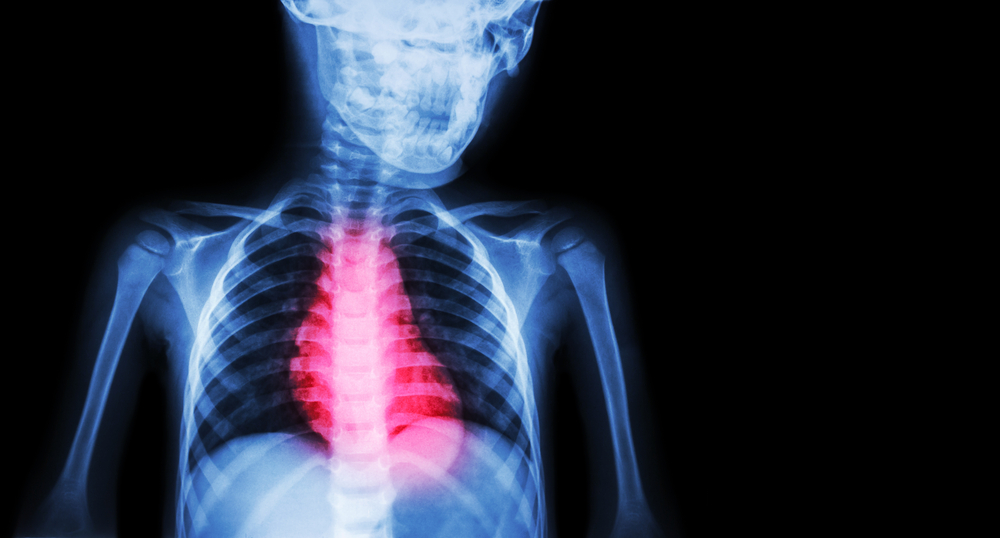

In this Healthed lecture, Associate Professor Stephan Foy provides a practical framework for investigation as they present in general practice.